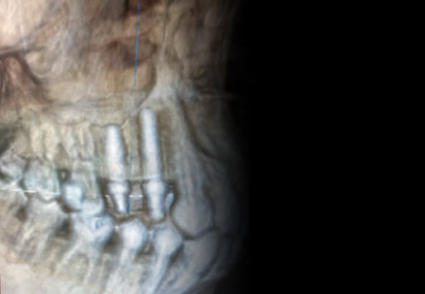

手術時に、神経を傷つけたり上顎洞内にドリルを迷入することを、最小限に出来ます。当院では、インプラント手術ナビゲーションシステムにより、インプラントを予定した理想的な位置に確実に埋め込むことのできる「X-ガイド」を導入しております。

●インプラントを理想的な位置・角度に埋め込むことができる

X-ガイドでは、撮影したCT画像をもとに、あらかじめコンピュータ上でインプラントを埋め込むベストな位置や角度をシミュレーションし、実際にその通りにインプラントを埋入するようナビゲートしてくれます。通常であればインプラントを埋め込むのが難しい症例であっても、ナビゲーションに従って手術を行うだけで、狙った位置に確実にインプラントを埋入することができます。

実際に肉眼で見ることのできない、骨の内部に存在する大事な神経や血管の位置を手術時に立体画像にてリアルタイムで把握できます。そのため、かつてのインプラント手術で起こりがちであった手術中に神経や血管を傷つける、というような人為的な事故を未然に防ぐことができ、安全に手術を進めていくことができます。

DTX Studio は、CTスキャンより得られた情報から立体画像を視覚化、検査診断、治療計画の立案、手術のシミュレーションが可能で、最終的な被せ物に至るまでインプラント治療をサポートします。DTX Studio上で作成した治療計画、シミュレーションは、3DダイナミックナビゲーションシステムとしてX-ガイドへと反映され、ドリルの位置をリアルタイムで360度モニター表示し、事前に作成したシミュレーション通りにインプラントの埋入を行うことができます。